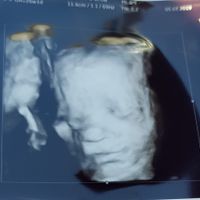

Eccolo qui 💙

Terry🌹 in Future mamme, Il 5 Marzo 2019 alle 18:44

Ciao ragazze, Stamattina abbiamo fatto la visita💙 il mio piccolo baby sta benissimo, si muoveva tanto ihih infatti questa é l unica foto che è riuacita a fare xke poi ha messo le manjne e i piedini in...